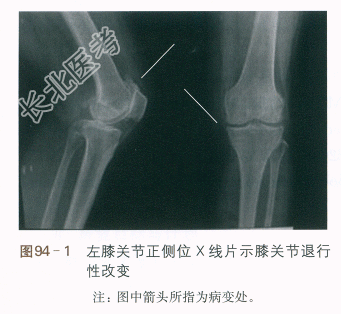

患者,女性,68岁,因“反复左膝关节疼痛伴活动受限6年,加重1周”入院。患者自诉6年前无明显诱因出现左膝关节疼痛,当时未予特别关注,休息后缓解。其后反复发作,逐渐加重,对天气变化敏感,劳累时加重,休息后可缓解,无其他部位疼痛和放射痛,曾予以药物、针灸、拔罐等治疗(具体治疗方法不详),病情反复发作。外院X线提示左膝关节退行性改变,如图94-1所示。近1周患者自觉左膝关节疼痛再次加重,伴左下肢乏力、膝关节不能屈伸,晨起出现左膝关节僵硬,时间少于30min,活动后改善。下蹲、上下楼梯困难。自发病以来患者神清、精神可,饮食二便正常。为求康复治疗,收入院。

血常规:WBC6.3×10⁹/L,GR67%,RBC3.5×10¹²/L,Hb125g/L,PLt205×10⁹/L。凝血功能:凝血酶原时间国际正常化比值1.1,D-二聚体1.6mg/L。血钾4.4mmol/L,血钠143mmol/L,血氯103mmol/L,血钙2.35mmol/L。X线检查提示关节间隙变窄,关节边缘骨赘形成。